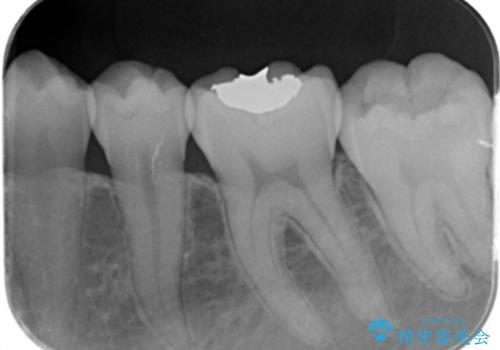

- 矯正を考えている患者様です。

歯の噛む面(咬合面)に虫歯が見られたので拡大鏡下で除去し

白い詰め物(e-maxインレー)にて治療しました。